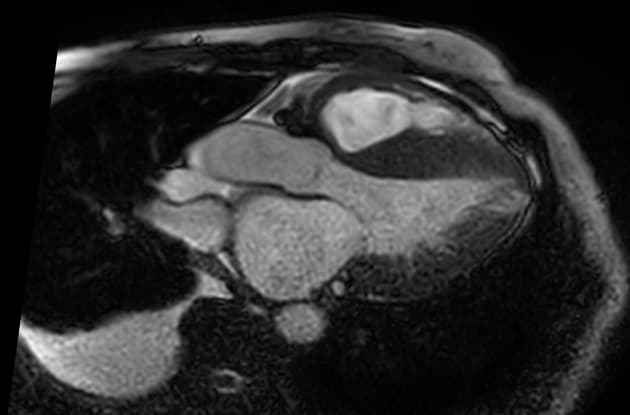

4ch T1 mapping

Phân tích hình thái và chức năng (endo-volume):

- Cung lượng tim: 5,2 L/phút

- Chỉ số tim: 2,7 L/phút/m²

- Chỉ số khối cơ thất trái (không tính cơ cột): 58 g/m²

- Độ dày vách liên thất: 13 mm

- Độ dày vách liên nhĩ: ~7 mm

- Rối loạn chức năng tâm trương với hình ảnh giãn thất bất thường trên quan sát trực tiếp

- Thành cơ tim thất trái và thất phải dày nhẹ, kèm theo vách liên nhĩ và thành tâm nhĩ phải dày

- Không có tổn thương van tim đáng kể

- Tràn dịch màng ngoài tim, đặc biệt quanh đỉnh tim và thành tự do thất phải

- Tràn dịch màng phổi hai bên (phải ~15 mm, trái ~20 mm)

Đặc tính mô cơ tim:

- STIR: tín hiệu tăng lan tỏa ở cơ tim, đặc biệt ở các đoạn vách và mặt dưới, gợi ý phù cơ tim (myocardial edema)

- Look-Locker: cơ tim được triệt tiêu trước buồng máu, gây khó khăn trong việc xác định thời gian đảo ngược (inversion time)

- PSIR/DIR: buồng máu tối và bắt thuốc muộn bằng gadolinium lan tỏa, một phần dưới nội tâm mạc, phân bố không theo vùng cấp máu động mạch vành, ảnh hưởng đến thành thất phải và tâm nhĩ

- Bản đồ T1 tự nhiên (native T1): 1175–1235 ms (z-score: 6–8)

- Thể tích ngoại bào (ECV): 46–52%

- Bản đồ T2: 58–62 ms (z-score: 3–4)

- Hình ảnh cộng hưởng từ tim (cardiac MRI) phù hợp với xơ cứng tinh thể tim (cardiac amyloidosis)

- Rối loạn chức năng tâm trương, gợi ý suy tim với phân suất tống máu bảo tồn (heart failure with preserved ejection fraction – HFpEF)

- Phù cơ tim trong bối cảnh xơ cứng tinh thể AL mang tiên lượng xấu